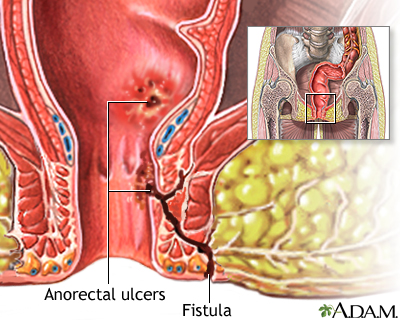

- Draining of pus, mucus, or stools from around the rectum or anus (caused by an abnormal opening in the skin called a fistula)

- Antibiotics to treat abscesses or fistulas.

- Fistulas (abnormal connections between the intestines and another area of the body)

- Fistulas in the bladder, skin, or vagina